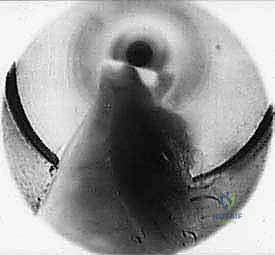

وداعًا لألم القدم المزمن: تخفيف الضغط بالمنظار أحادي المدخل لورم مورتون مع الأستاذ الدكتور محمد هطيف

اكتشف علاج ورم مورتون بالمنظار أحادي المدخل مع الأستاذ الدكتور محمد هطيف في صنعاء. تقنية حديثة لتخفيف الألم، شق صغير، تعافٍ أسرع، وحماية الع…